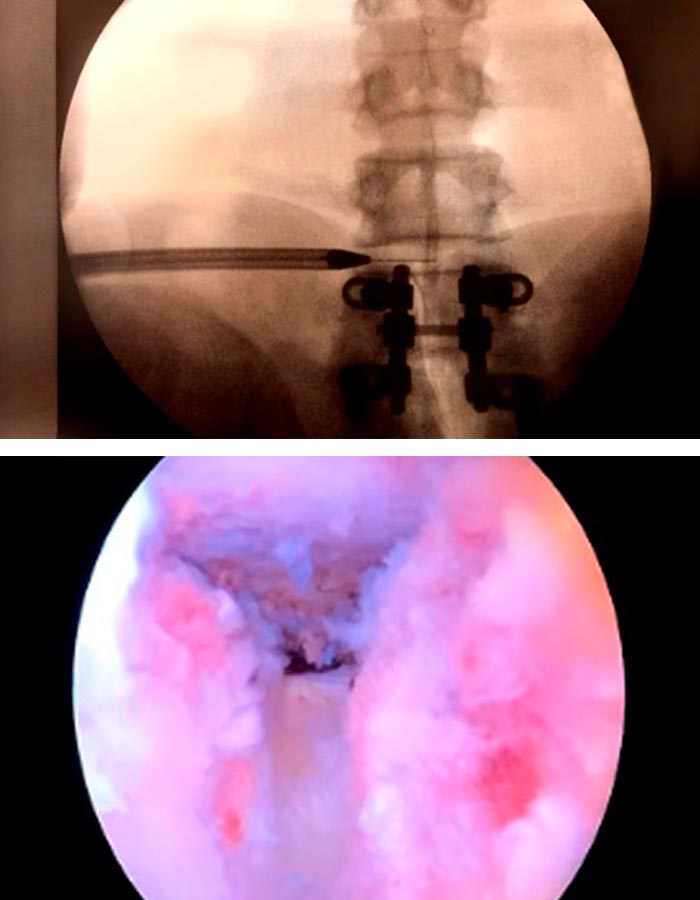

La cirugía mínimamente invasiva de endoscopia de avanzada de columna se lleva a cabo en unas dos horas a través de un portal de unos 3mm, situado en la parte posterior de la columna :

1. Se introduce una aguja guía que nos ayudará a introducir un dilatador para acceder a la zona de trabajo sin dañar ningún tipo de tejido.

2. Una vez localizado el nivel y visualizado el disco procedemos a extraer la hernia muy despacio para que no se desprendan nuevos trozos.

Endoscopia de columna para extraccion hernia discal

Cirugia endoscopia de columna